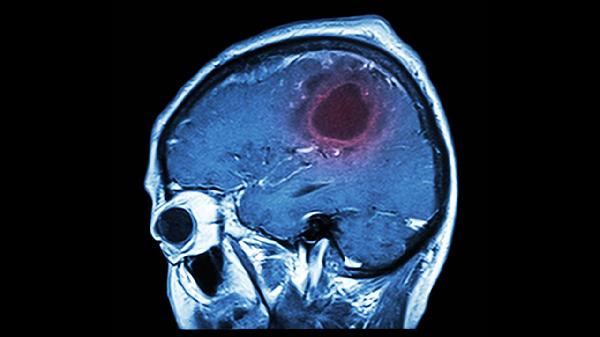

日常应注意保持规律作息与均衡饮食,适量补充核桃、深海鱼等富含不饱和脂肪酸的食物。工作间歇可做颈部保健操促进血液循环,持续两周以上不缓解或伴随剧烈头痛、呕吐等症状时,需及时进行头颅CT等检查排除器质性疾病。心理因素引起者可尝试心理咨询或沙盘治疗等干预方式。